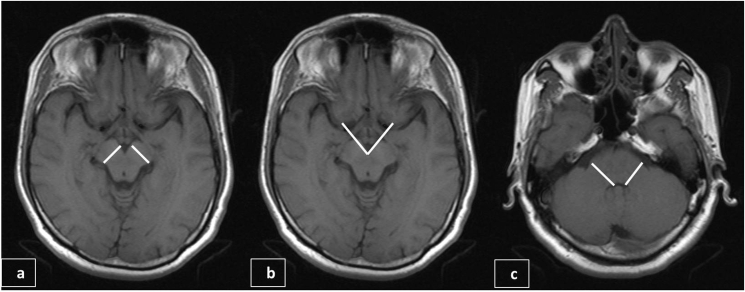

T1WI axial images (Fig. 1)

Cerebral peduncle (CP) transverse thickness: Maximum thickness of cerebral peduncle perpendicular to its long axis was noted on both sides (Fig. 1a).

Interpeduncular angle (IPA) formed between cerebral peduncles (Fig. 1b).

Middle cerebellar peduncle (MCP) transverse thickness: Maximum thickness of each middle cerebellar peduncle perpendicular to its long axis was noted on both sides (Fig. 1c).

Fig. 1.

T1WI Axial images at the level of cerebral peduncles depicting the technique of measuring cerebral peduncle thickness (a) and interpeduncular angle (b) and at the level of middle cerebellar peduncles depicting the technique of measuring middle cerebellar peduncle thickness (c).